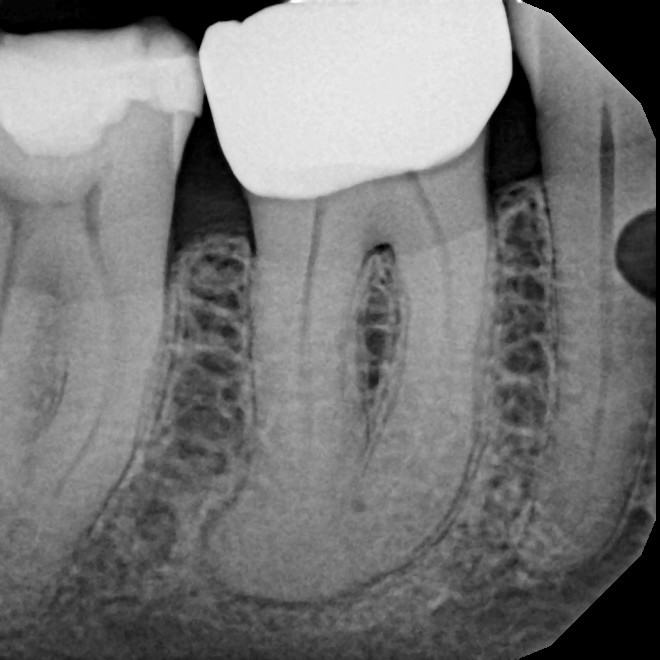

Before & After